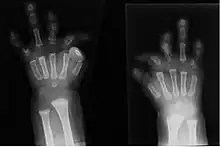

Radiographie montrant un cas sévère de brachydactylie